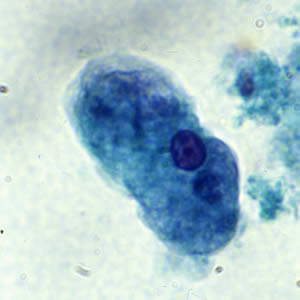

E. histolytica trophozoite

single nucleus with centrally placed karyosome. Cytoplasm contains ingested RBC’s.